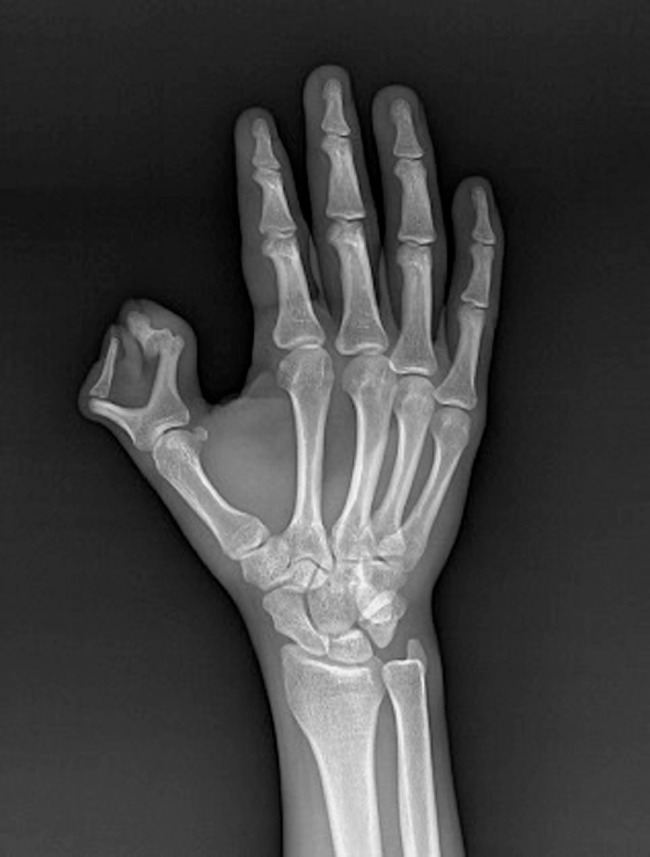

Fig. 3.

Anteroposterior radiograph of the right hand depicts bifid proximal phalanx and duplication of the distal phalanx of the thumb consistent with Wassel type III polydactyly.